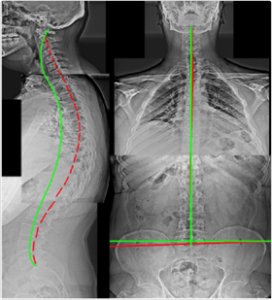

Case 3 — 46yo Male: Chronic Neck & Back Problems

Figure 3. Thoracic Hyperkyphosis, Posterior Thoracic Translation, Anterior Head Translation, Cervical Hypolordosis, Anatomical Leg Length Discrepancy. Leg length discrepancy causes compensatory scoliosis — only confirmed on AP X-ray.